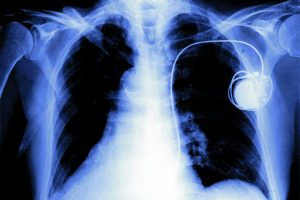

Η δύσπνοια έχει συνδυαστεί με τις αναπνευστικές παθήσεις όπως η Χρόνια Αποφρακτική Πνευμονοπάθεια (ΧΑΠ), το βρογχικό άσθμα, τις διάμεσες πνευμονοπάθειες, τις διαταραχές του ύπνου και τις λοιμώξεις του αναπνευστικου. Εντούτοις η κυρία Τσικρικά τονίζει πως ο κατάλογος των αιτιολογικών παραγόντων είναι μακρύς, όμως πιθανά να μη γίνουν άμεσα αντιληπτοί λόγω υποτίμησης των συμπτωμάτων. Πιο συγκεκριμένα […]